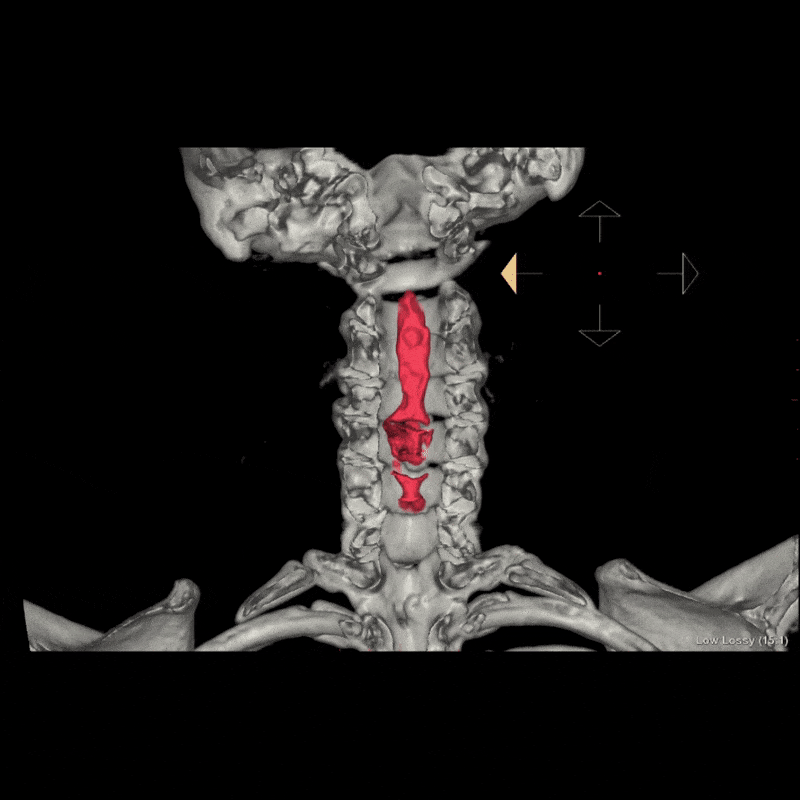

A patient with progressive neck pain and neurologic symptoms was referred to the 3DQ Lab for imaging due to concern for narrowing of the cervical spinal canal. Prior imaging demonstrated extensive ossification of the posterior longitudinal ligament from C2 through C6, resulting in spinal canal stenosis. Additional imaging was requested to better characterize the disease and support surgical planning.

Ossification of the posterior longitudinal ligament, commonly referred to as OPLL, occurs when ligament tissue that is normally flexible gradually transforms into bone. When this occurs, it can reduce the space available for the spinal cord. Because the posterior longitudinal ligament lies directly in front of the cord, OPLL can have a significant impact on neurologic function.

A CT scan of the cervical spine was obtained to further evaluate the presence and severity of OPLL. CT is well suited for this assessment because it clearly depicts bone and calcified structures, allowing the ossified ligament to be easily distinguished from surrounding soft tissues. The scan confirmed extensive OPLL from C2 through C6 with severe spinal canal stenosis.

Using the CT dataset, a radiologic technologist processed the images to create a series of advanced visualizations that highlight the distribution of ossification and its relationship to surrounding anatomy. These images provide different perspectives of the cervical spine and help translate cross-sectional findings into more intuitive views.

Volume rendering and cutplane techniques were also used to create views that expose the interior of the spinal canal. These images show how the ossified posterior longitudinal ligament occupies space normally reserved for the spinal cord, offering a clearer sense of the degree of compression. All of these images were provided to the surgical team to add context and support presurgical planning by illustrating the spatial impact of the disease.